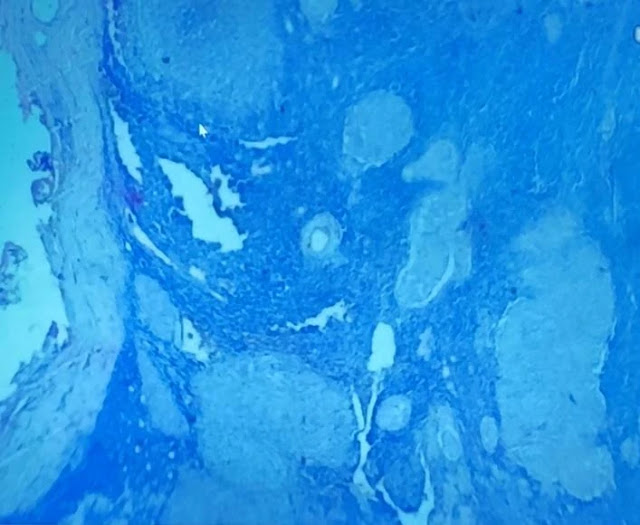

08. Lymph Node and Capsule of the Lymph node

Under a microscope, the lymph node shows multiple distinct regions, such as the medulla, cortex, and paracortex.

A lymph node's capsule is visible as a thin layer of connective tissue encircling the node's outer edge.

In addition to carrying blood vessels and nerves that supply the node, it offers structural support. The capsule is essential to the preservation of the lymph node's structure and functionality.

Sub Capsular Sinus of the Lymph Nodes (empty space)

the separation between the capsule and the lymph node parenchyma. This sinus, which is lined with specialized cells, is the first location where lymph enters the lymph node. It acts as a filter, collecting foreign particles and antigens for immune cells to analyze and respond to appropriately.

Granuloma of Lymph Nodes

often notice a ring of lymphocytes surrounding a collection of immune cells, primarily macrophages. Compact clusters or nodules are common forms for these structures, though they can vary in size and shape.

Granulomas are a symptom of chronic inflammation and can be caused by a range of infectious and non-infectious agents, including bacteria, fungi, and foreign substances.